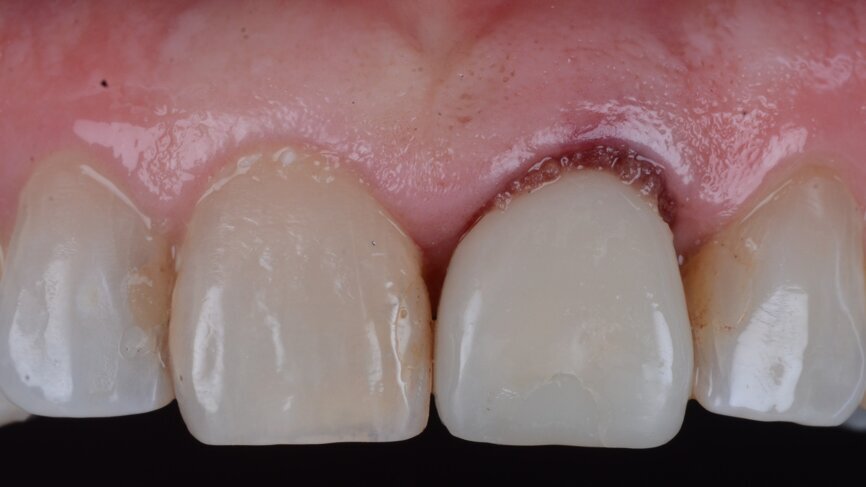

A 53-year-old female patient presented to the office with a fractured left central incisor which had been repeatedly bonded to a ceramic crown (Figs. 1 & 2). Anamneses and examination established good systemic and oral health, a well-balanced occlusion and no smoking habits. Cone beam computed tomography (CBCT) and a periapical radiograph showed external root resorption with very limited insertion into the alveolar bone, insufficient for adequate conventional intra-radicular post placement (Figs. 3 & 4). Considering that the fractured tooth was in the aesthetic zone, the patient requested restoration in the safest and fastest way possible.

Fig. 2: Initial situation, intra-oral view.